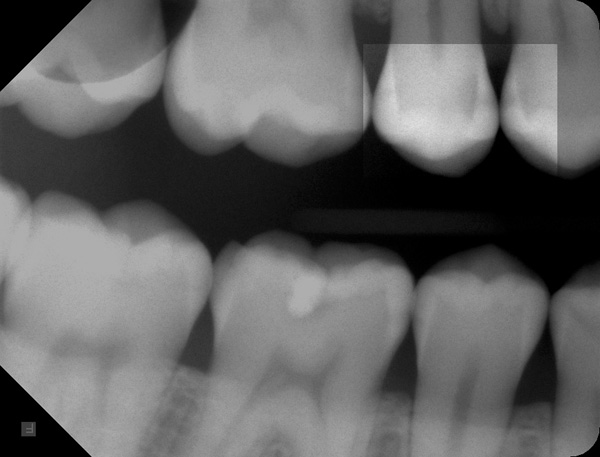

Der Patient kam als Neuaufnahme mit Schmerzen in die Sprechstunde. Das Röntgenbild ergab unter anderen Befunden eine Zahnzwischenraumkaries an den Zähnen 14 und 15.

Das nächste Foto zeigt einen noch kleinen Defekt an Zahn 15 distal. Im Röntgenbild ist dieser Schaden nur schwach zu sehen.